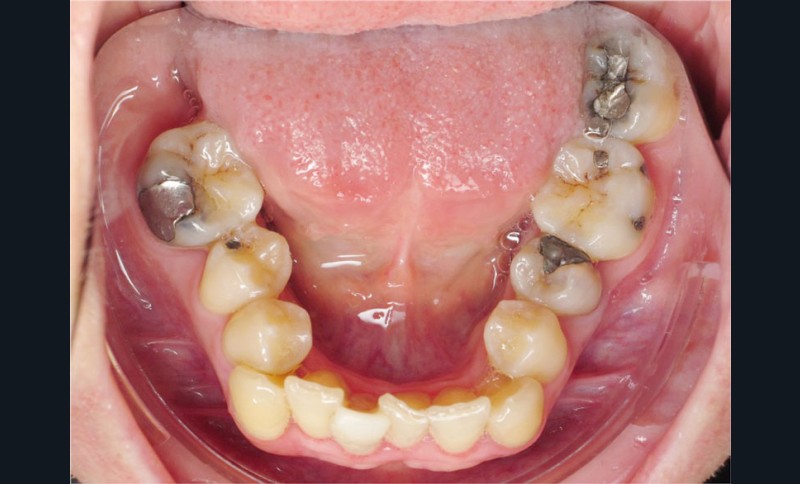

Cas n° 2

Nous lui avons donc proposé un traitement d’alignement avec maintien des 14 et 24 en position de 13 et 23 et optimisation du torque pour favoriser un développement des arcades et chercher à améliorer le sourire et le soutien labial.

La patiente donne son accord pour un appareillage Damon Insignia métal qui permet une individualisation complète des brackets dans les 3 sens de l’espace.

Un appareillage Damon métal a été mis en place, réalisé à partir d’un set up numérique Insignia pour obtenir un contrôle précis des torques et de la forme d’arcade et réduire le temps de finition grâce à un collage indirect très précis.

De larges surélévations postérieures étalées ont été mises en place et la patiente a porté des élastiques précoces suivant les principes de la technique Damon. Les 14 et 24 rempliront le rôle des 13 et 23.

L’objectif, en utilisant la technique Insignia est de réduire le temps de traitement de 28 à 18 mois avec 12 rendez-vous (fig. 5 à 14).